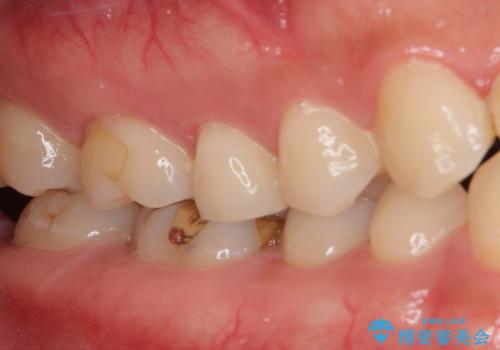

左上奥と右下奥に治療中の歯があり、虫歯を取っている途中で仮詰めの材料が充填されている状態でした。

仮詰め材を外すと虫歯が残っていたので、全てを取り除いた後に、ゴールドインレーの型どりを行いました。